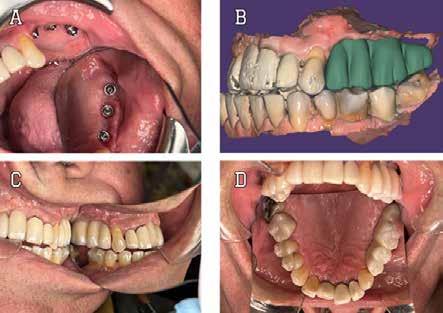

This patient case report presents a complex case including an atrophic posterior maxillary region, a history of multiple failed implants, the complete lack of a sinus floor and the goal of rehabilitating normal masticatory function. Extensive grafting, 3D modeling, prosthetic splinting, and extra-maxillary anchorage were utilized in management of this case to maximize primary stability.

It must be emphasized in this implant dentistry that prosthetic design should dictate implant placement. Any large edentulous span likely requires multiple implants for anchorage. A digital wax-up helps determine the optimal location of the placement of the implants. Teeth with a questionable prognosis may need to be sacrificed to optimize the prosthetic design. Both the inter-implant distance as well as the distance between implants and natural dentition needs to be taken into account to promote cleanability. Implant placement based on the wax-up may help identify the need for additional bone grafting in horizontal as well as

vertical components. Irregular bony topography, implants, dentition located in close proximity, and suboptimal prosthetic design may lead to plaque-accumulating spaces. This can affect oral hygiene maintenance, and may ultimately lead to failure of the implants and prosthesis.12

#13, #14 for ridge preservation. At a later date, three implant-supported crowns in close proximity were placed in these sites. Notably, the crowns were non-splinted. (Fig. 1).

In July 2021, the patient presented with mobile implants #12, #13 and #14 to his dental practitioner (Fig. 2). The implants were removed without bone grafting.

The patient received an interim removable partial denture and presented to the oral surgery clinic for evaluation for a fixed solution. At the time of initial consultation (September 2021), it was determined that failure of the implants was due in part to excessive occlusal forces as well as lack of proper hygiene maintenance and recall by the patient. For success, prior restoration design should have minimized difficult-to-reach areas for brushing